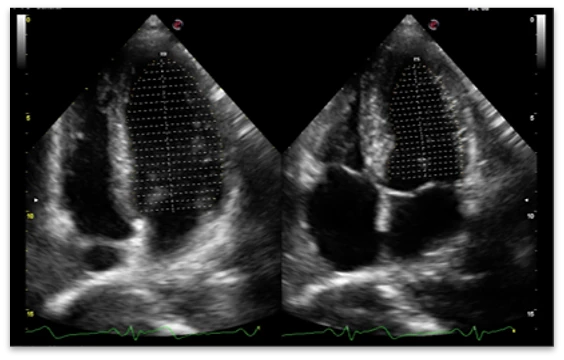

Radiologiya va kardiologiyada kontrast moddalar bilan ishlashda perfuziya parametrlarini baholash uchun CUES (CnTI/LVO)